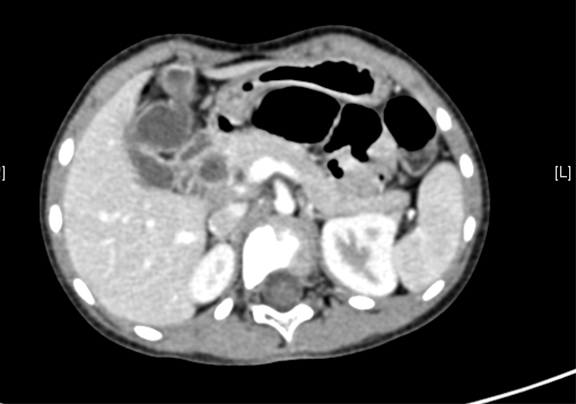

术前CT检查:

动脉期

静脉期

平衡期